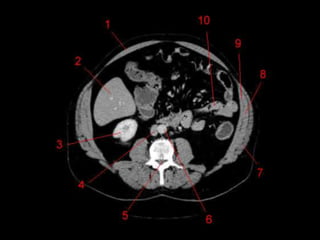

Subdivisão Funcional

• Os oito segmentos são divididos:

– A primeira divisão é realizada dividindo através da

Porta Hepática, em esquerdo (I a IV) e direito (V a VIII)

– A divisão é feita baseada em um relógio

– Caudado é o segmento I

– No ‘lobo’ esquerdo, o IV separa-se do II e do III pela

veia hepática esquerda, representado

anatomicamente pelo ligamento falciforme.

– II e III se dividem através de uma linha imaginária

transversal na altura da porta hepática.

– No ‘lobo’ direito, se divide os segmentos através de

uma linha transversal e pela veia hepática direita.

Subdivisão Funcional • Osoito segmentos são divididos: – A primeira divisão é realizada dividindo através da Porta Hepática, em esquerdo (I a IV) e direito (V a VIII) – A divisão é feita baseada em um relógio – Caudado é o segmento I – No ‘lobo’ esquerdo, o IV separa-se do II e do III pela veia hepática esquerda, representado anatomicamente pelo ligamento falciforme. – II e III se dividem através de uma linha imaginária transversal na altura da porta hepática. – No ‘lobo’ direito, se divide os segmentos através de uma linha transversal e pela veia hepática direita.